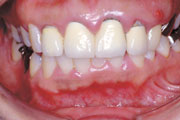

症例4

45歳男性です。奥歯の詰め物がはずれて来院されました。明らかに歯肉が腫れています。

精密検査を勧め、ご了解いただいた上で検査をして治療に入りました。右の写真は治療開始2ヵ月後です。